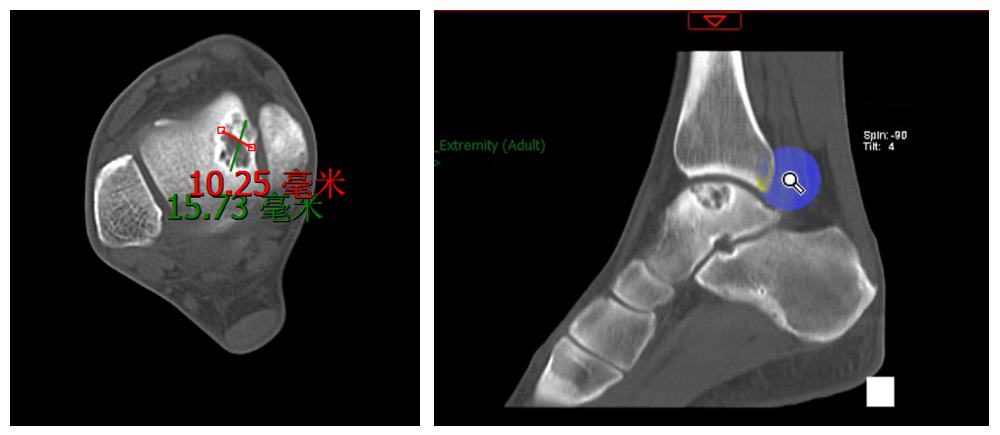

距骨软骨损伤病灶(病灶位于4区,内踝遮挡,常规术式难以显露)

术前,团队基于患者CT数据,1:1精准打印出患侧踝关节模型,并依此设计制作了个性化的截骨导板。这一技术实现了对截骨位置、角度及范围的量化预规划,使手术方案更加直观、可控。